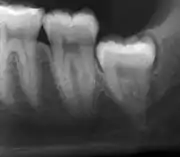

The diagnosis of impaction can be made clinically if enough of the wisdom tooth is visible to determine its angulation, depth, and if the patient is old enough that further eruption or uprighting is unlikely. Wisdom teeth continue to move to the age of 25 years old due to eruption, and then continue some later movement owing to periodontal disease.[18]

If the tooth cannot be assessed with clinical exam alone, the diagnosis is made using either a panoramic radiograph or cone-beam CT. Where unerupted wisdom teeth still have eruption potential several predictors are used to determine the chance of the teeth becoming impacted. The ratio of space between the tooth crown length and the amount of space available, the angle of the teeth compared to the other teeth are the two most commonly used predictors, with the space ratio being the most accurate. Despite the capacity for movement into early adulthood, the likelihood that the tooth will become impacted can be predicted when the ratio of space available to the length of the crown of the tooth is under 1.[5]:141